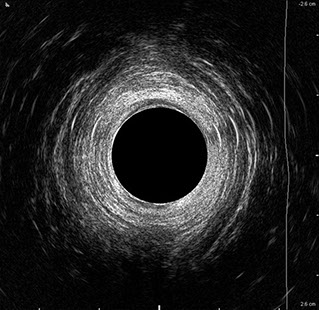

L’ecografia transanale è un esame diagnostico per immagini che consiste nell’introduzione di un trasduttore ad ultrasuoni. Le immagini qualitativamente migliori del canale anale sono ottenute usando un trasduttore rotante, montato in un manipolo rigido, che fornisce un’immagine a 360°. Con le apparecchiature più moderne è anche possibile ottenere immagini tridimensionali.

L’ecografia transanale permette di distinguere la sottomucosa che riveste il canale anale, lo sfintere anale interno, e lo sfintere anale esterno.

Proctal dispone di apparecchiatura per ecografia endoanale 3D con sonda rotante.

Sezione Longitudinale 3D con Tramite Fistoloso Intersfinterico Basso Anteriore Semplice